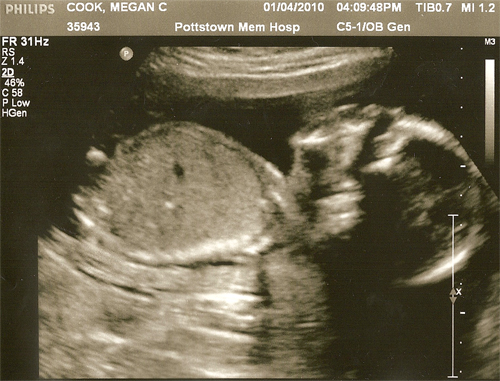

On January 4th, 2010 Megan and I visited the Pottstown Memorial Hospital for Lima’s second Ultrasound.

Honestly, it wasn’t as emotional for Megan and I ask Lima’s first Ultrasound – this was probably becauseĀ Megan couldn’t see the screen and I continued to ask why there were so many teeth. š Obviously baby’s don’t have teeth in the womb but I sware to you it looked like a xray ((yes, I know we were at an Ultrasound – trying to make a point here)) of someone’s upper and lower teeth.Ā Sometimes with a third row in the middle.Ā I believe this was probably the spine andĀ a weird Ultrasound reflection issue that has some technical name attached to it.

Anyway, here are pictures!